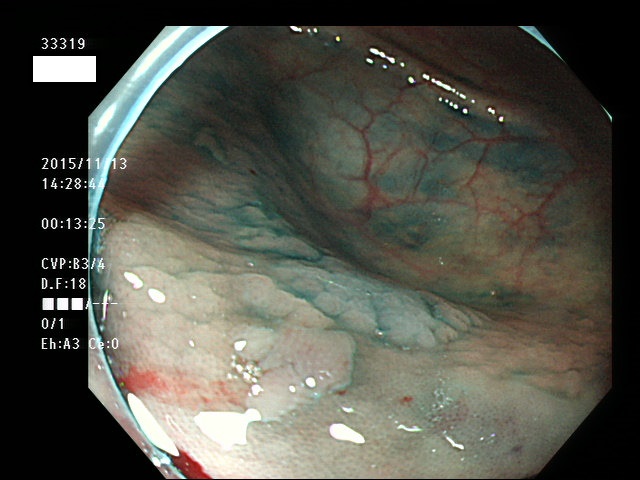

上記100名より抽出した平坦・陥凹型腺腫(=癌化の危険が高いが見落としやすい病変)の内視鏡写真